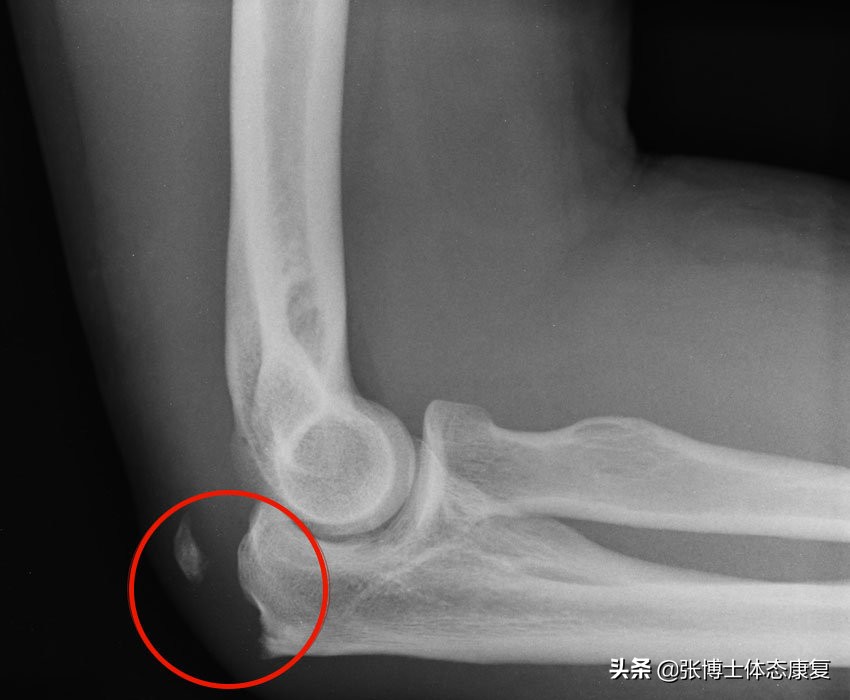

3.剥脱性骨软骨炎

包括软骨碎裂,有时还包括肘关节内潜在的骨头碎裂。这在青少年中很常见,尤其是那些参与投掷运动的青少年,主要是由于骨头的末端还没有完全硬化。症状包括肘部被锁死、出现“咔哒”声、肿胀、疼痛(尤其是活动后)和功能丧失。